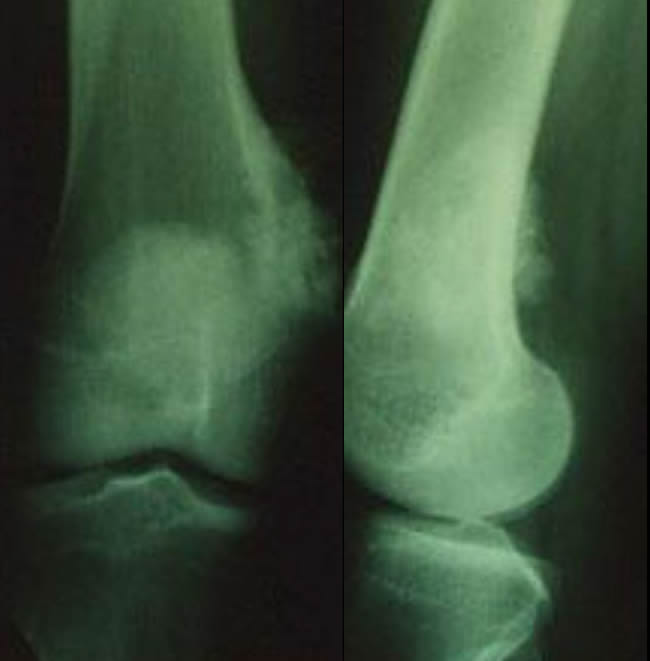

Aspect trompeur épiphysaire et lytique évoquant une tumeur à cellules géantes

Jeune femme de 25 ans souffrant de son genou selon un rythme mécanique depuis 3 mois.